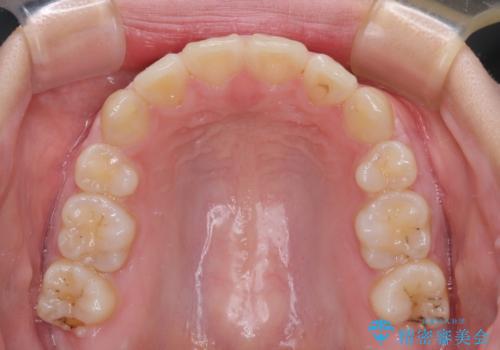

上下ともに歯列が前方に突出していたため、上下左右の第一小臼歯4本を抜去する方針(既に上顎は抜歯されています)で、ワイヤー装置による矯正治療を行うこととしました。

舌の突出癖があり、咬合力も強かったため、治療期間は長くなることが懸念されましたが、舌のトレーニングをしっかりと行っていただいたこともあり、2年弱で治療を終えることができました。